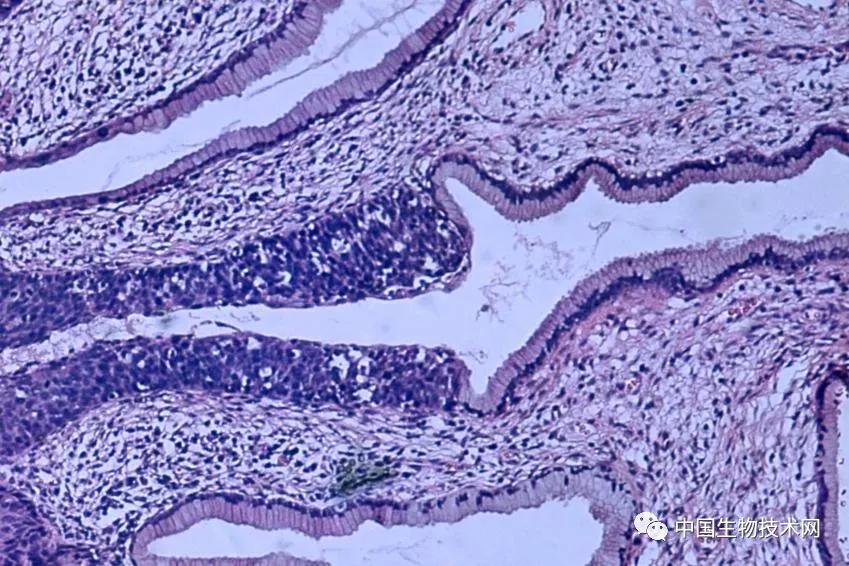

2018年,世界卫生组织发出了消除宫颈癌这一公共卫生问题的全球呼吁,并设定了每10万名妇女患病人数不超过4人的目标。由于接种了预防HPV的疫苗,并通过筛查及早发现,使得宫颈癌成为最可预防和治疗的癌症之一。

2月10日,发表在《柳叶刀公共卫生》上的一项新研究显示,将美国的宫颈癌筛查覆盖率提高到90%,可以加快消除这种疾病,而且每年还能避免一千多个新增病例。这项由美国哈佛大学T.H. Chan公共卫生学院牵头的研究发现,与目前的筛查和人乳头瘤病毒(HPV)疫苗接种水平相比,这将是加速消除该疾病最有效的方法。